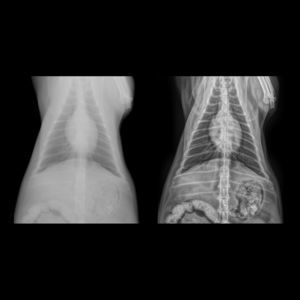

... Dys4Vet es un software desarrollado para apoyar el diagnóstico de la displasia de cadera canina mediante Inteligencia Artificial (IA) aplicada a imágenes radiográficas. Calcula: • Congruencia de cadera • Ángulo de Norberg • ...